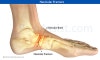

주상골 골절(Navicular fracture) : 자전거를 타고 가다 넘어진 뒤 발 가운데가 아파요

종족골 골절 중 가장 흔한 골절입니다.

중족부의 막연한 통증과 부종을 호소합니다.

중족부에 압통이 있습니다.